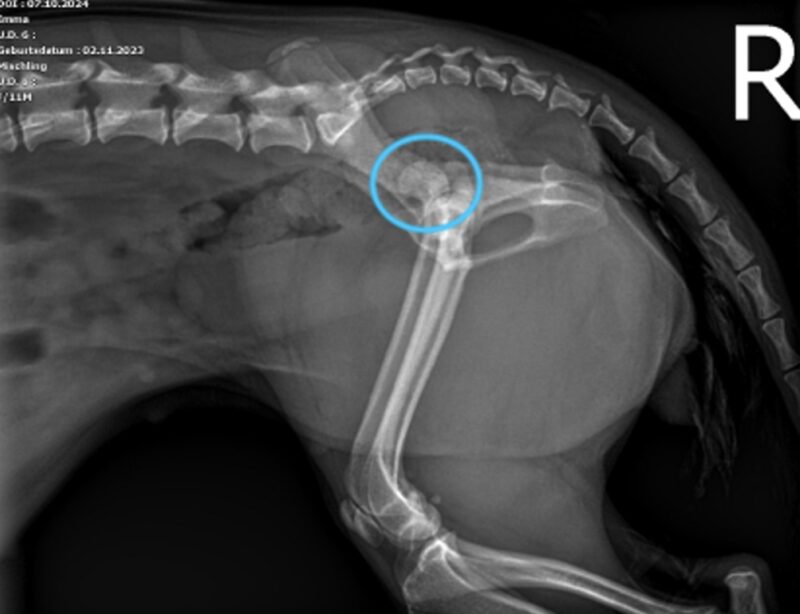

Der rechte Femurkopf ist vollständig aus dem Acetabulum luxiert und nach kranial und dorsal verschoben (blaue Kreise). Die Weichteile des linken Femurs sind geringgradig verdickt. Im linken lateralen Aspekt der abdominalen Wand ist eine minimale Luftansammlung erkennbar. Beidseits sind die Coxofemoralgelenke geringgradig nach außen rotiert, welches eine laterale Positionierung der Patellae verursacht. Im rechten Kniegelenk befindet sich die Patella jedoch in medialer Position (blauer Pfeilkopf). Es ist unklar, ob ob diese traumatisch oder rasse-bedingt entstanden ist und welcher Grad der Patellaluxation vorliegt. Die sichtbaren caudalen abdominalen Organe sind ohne besonderen Befund.

Es handelt sich um eine akute, geschlossene, monostotische, segmentale Fraktur des rechten Os pubis, eine kraniodorsale Luxation des linken Femurs, eine mediale Luxation der rechten Patella und eine geringgradige Weichteilschwellung des linken Oberschenkels.